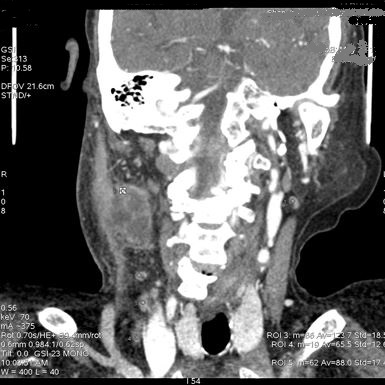

颈部间隙多发肿大淋巴结,能谱曲线表达高度相似,提示性质相同——炎性感染。

小结 1、CNR(最佳对比信号噪声比):可以准确把握颈部软组织病变的最佳单能成像; 2、能谱曲线:有助于颈部不同软组织之间性质差异的鉴别; 3、碘-水基物质分析:可对病变进行准确定量分析,同时还有助于疗效评估。